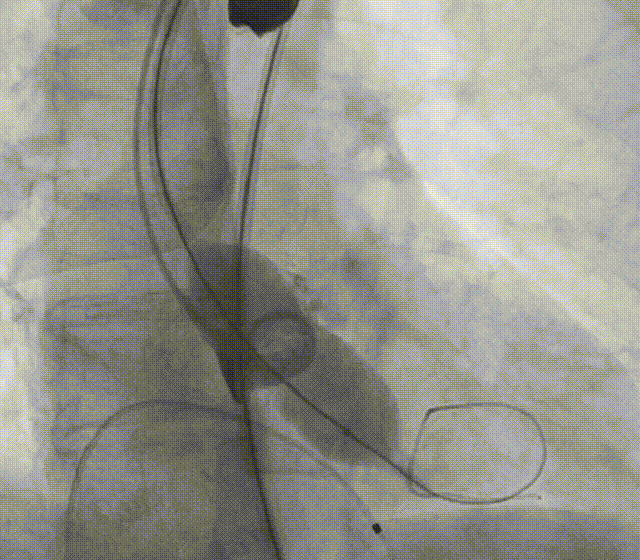

手术过程

全麻下建立双侧股动脉入路,以右股动脉为主;导丝跨瓣后置换猪尾导管,确定共平面。

图片

使用20mm球囊进行预扩,无腰征无反流。